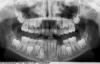

Svetiks11 Опубликовано 23 апреля, 2011 Поделиться Опубликовано 23 апреля, 2011 Добрый день! Нужен совет по снимку. Вопрос по верхним шестеркам, нужно ли срочно лечить кариес или можно понаблюдать и провести минерализацию зубов? Ссылка на комментарий

juli63 Опубликовано 23 апреля, 2011 Поделиться Опубликовано 23 апреля, 2011 Добрый день! Нужен совет по снимку. Вопрос по верхним шестеркам, нужно ли срочно лечить кариес или можно понаблюдать и провести минерализацию зубов? я по снимку не могу определить какой там кариес.когда процесс на самой ранней стадии развития, тогда минерализация зубов показана. а когда уже есть дефект эмали и дентина-только лечение. раньше начнете-обойдетесь минимальными потерями. Ссылка на комментарий

juli63 Опубликовано 23 апреля, 2011 Поделиться Опубликовано 23 апреля, 2011 А по снимку кариес видно, что он там есть?чтобы рассмотреть кариес-нужен прикусной снимок. Ссылка на комментарий

juli63 Опубликовано 23 апреля, 2011 Поделиться Опубликовано 23 апреля, 2011 Ясно, спасибо, просто один врач говорит надо лечить кариес, второй просто его не видит, вот и не знаю даже...в вашем случае поможет фото и прикусой снимок Ссылка на комментарий